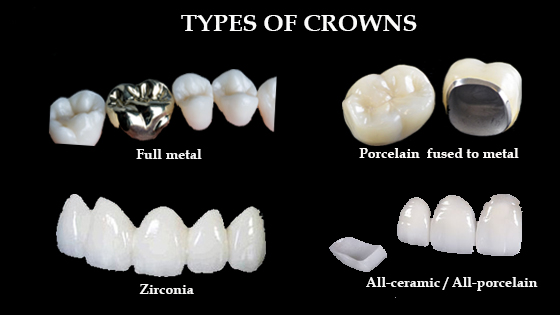

Discover the Different Types of Dental Crowns: A Complete Guide

Welcome to an insightful exploration of dental crowns! Whether you’re considering ways to enhance your smile or restore the function of your teeth, understanding the

Dental Crowns: Everything You Need to Know

A dental crown is a tooth-shaped cap that is placed over a damaged or decayed tooth to restore its shape, size, and strength. It is